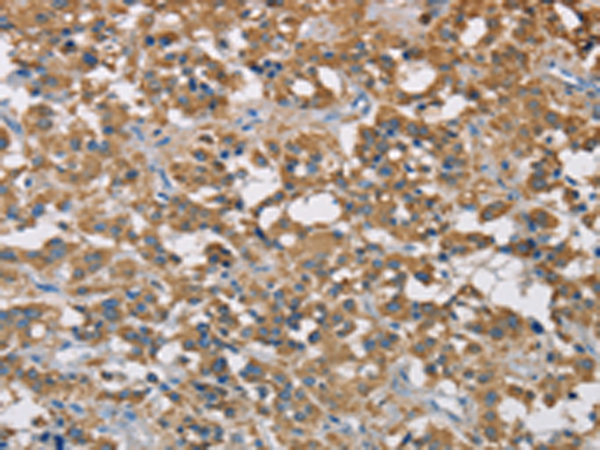

分类: 科研抗体货号: P08199别名:应用: IHC反应种属: Human